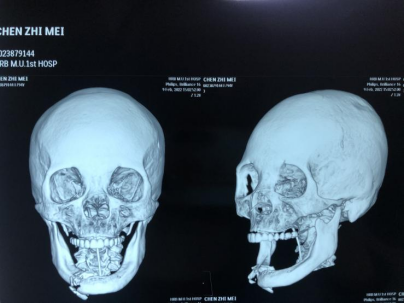

患者为94岁女性,因车祸致下颌骨骨折,伤后不能咀嚼进食,颌面骨三维ct示右下颌骨粉碎性骨折。家属通过网络平台向胡腾龙求助,科室立即启动转诊流程,患者由外地迅速转入病房。

入院检查后确定为右下颌骨颏孔区骨折,需手术治疗恢复患者下颌骨的连续性。下颌骨骨折切开复位内固定术属于口腔颌面外科常规手术,但因患者年龄较大,术前须仔细评估患者能否承受全麻手术带来的风险,术前经过科室的充分讨论及麻醉科林世升教授的麻醉评估,制定了详细的手术计划。